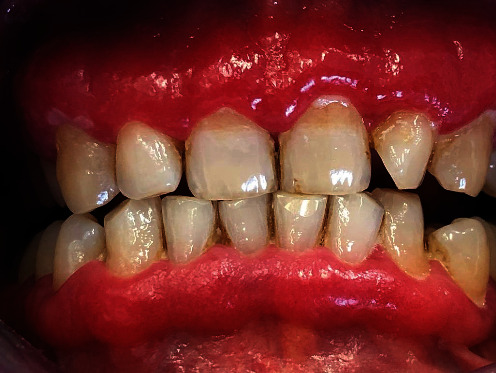

The local objective clinical examination revealed intense edema and erythema localized to the adherent vestibular gingival mucosa, from elements 1.5 to 2.5 (Figure 1). The periodontal charting showed probing pocket depth <3 mm without loss of clinical attachment level, in the presence of intense bleeding. First and second level blood chemistry was prescribed and showed positivity for Proteinase 3 antibodies.

Figure 1.

Intense edema and erythema localized to the adherent vestibular gingival mucosa, from elements 1.5 to 2.5.